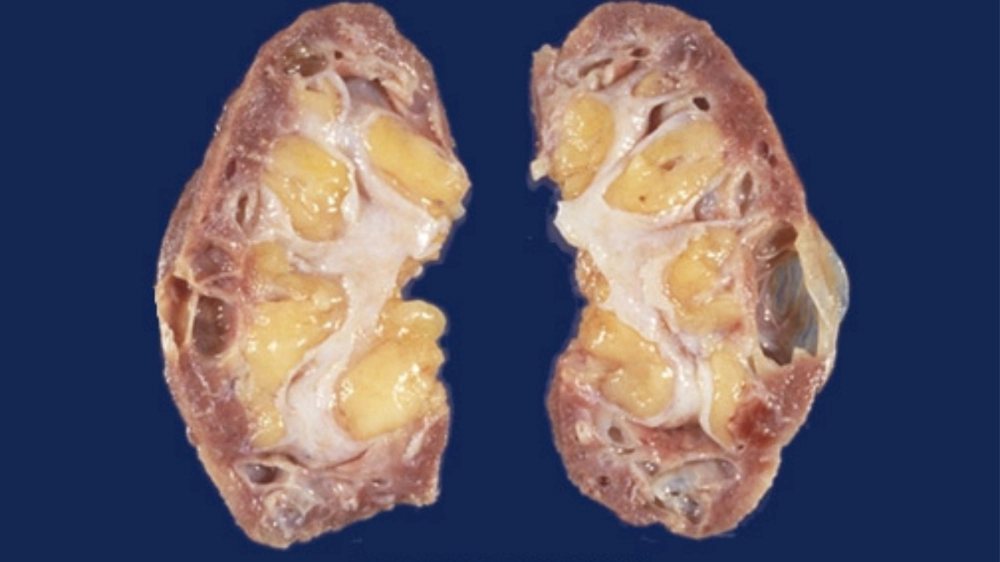

Cấu trúc cầu thận bị tổn thương